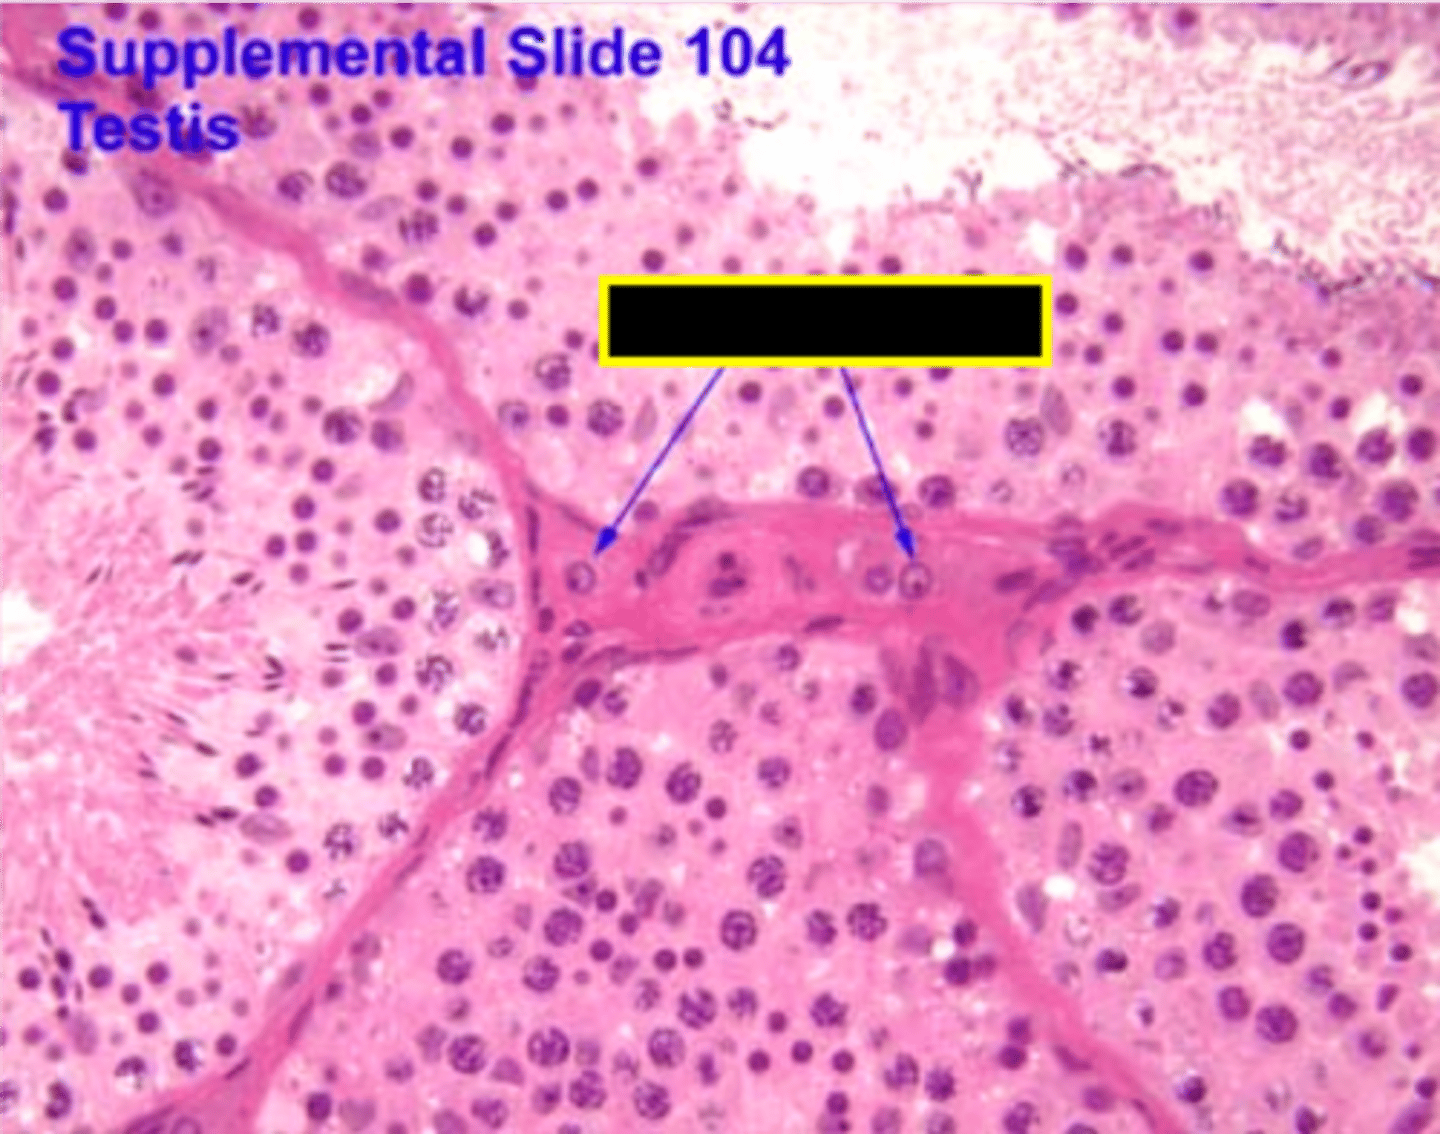

Leydig cell

Leydig cell

Spermatogenesis

Spermatogenesis

Spermatogonia

Primary spermatocyte

Spermatogonia

Spermatid (early)

Primary spermatocyte

Spermatid (late)

Spermatid (early)

Spermatozoon

Spermatid (late)

Spermatozoa